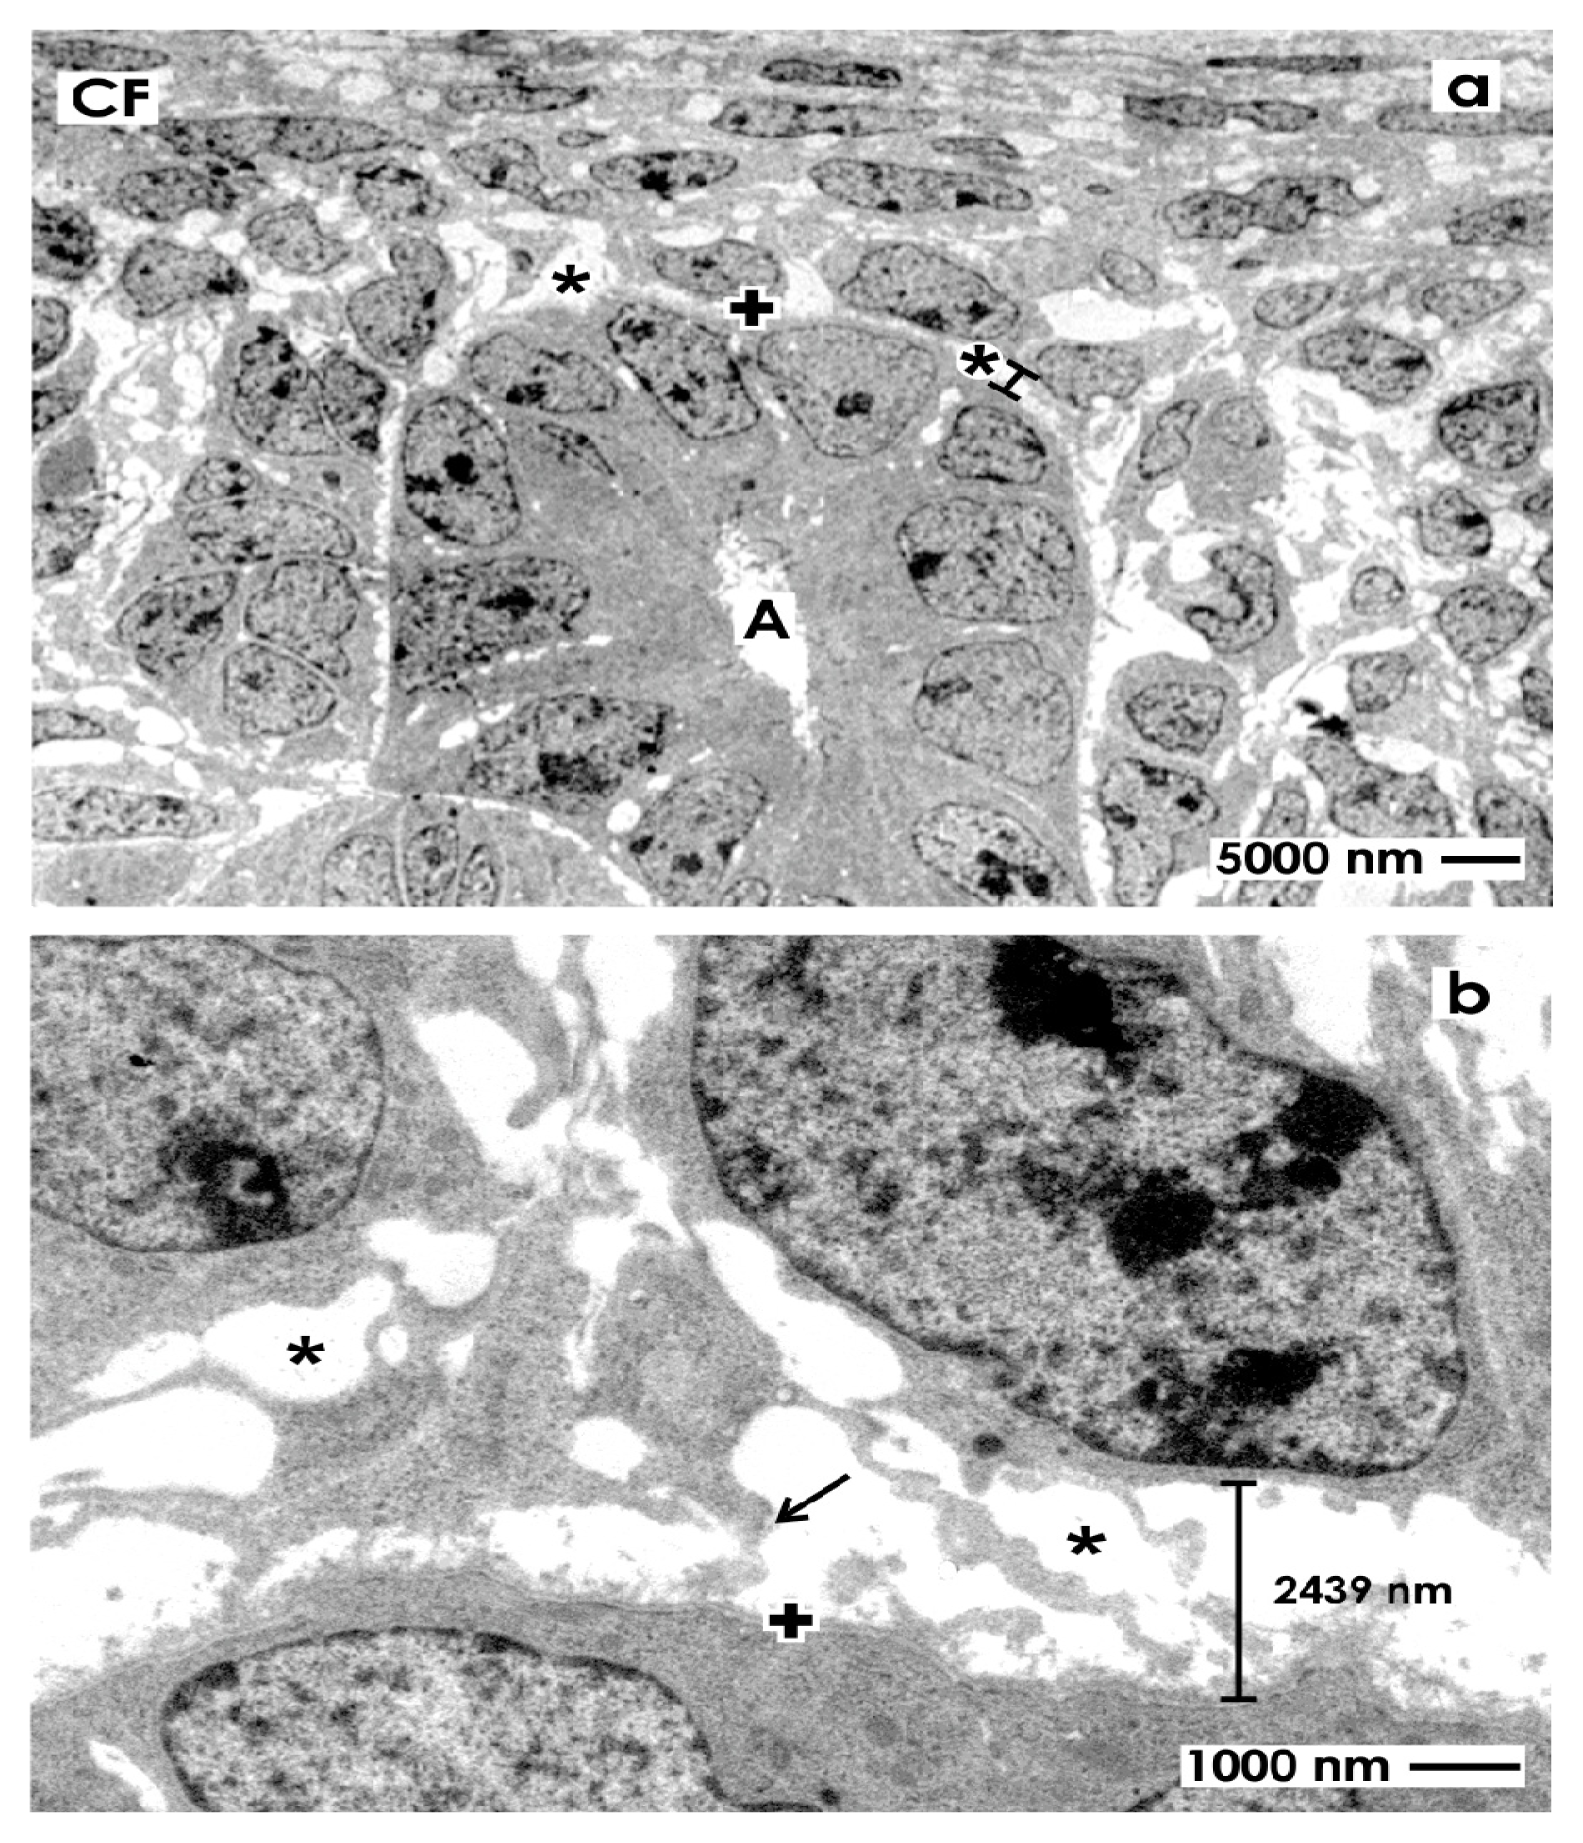

To better illustrate the omnipresent interstitial interface within the renal stem/progenitor cell niche, specimens of embryonic parenchyma were traditionally fixed with glutaraldehyde (GA) to investigate ultrathin sections under low magnification in transmission electron microscopy (Figure 2).

Figure 2.

Transmission electron microscopy of the renal stem/progenitor cell niche in neonatal rabbit kidney after fixation in glutaraldehyde (GA). (a) Low magnification depicts that epithelial stem/progenitor cells are enclosed by the basal lamina (+) at the collecting ducts (CD) ampulla (A) tip. The soma of mesenchymal stem/progenitor cells is separated from epithelial cells by the interstitial interface (asterisk/spacer); (b) Higher magnification shows that epithelial and mesenchymal stem/progenitor cells are kept in this typical case at a distance of 2439 nm by the bright interstitial interface.

A surface view shows typical features within the renal stem/progenitor cell niche. Integrated within the tip of a CD ampulla (A), epithelial stem/progenitor cells are found (Figure 2a). The basal aspect of the ampulla is surrounded by mesenchymal stem/progenitor cells. Both types of cells are separated by the bright interstitial interface. Higher magnification illustrates that mesenchymal stem/progenitor cells send out filigree cell projections, which cross the interstitial interface to contact at irregular distances the basal lamina at the CD ampulla tip (Figure 2b). Further, the distance between the basal lamina at the CD ampulla tip, mesenchymal stem/progenitor cells and their crossing projections is about 2400 nm, appears bright and exhibits no recognizable extracellular matrix. Finally, in all of the cases was seen that the interstitial interface within the renal stem/progenitor cell niche keeps epithelial in distinct distance to mesenchymal cells. As a consequence, clustering or close contacts between cells was never observed.